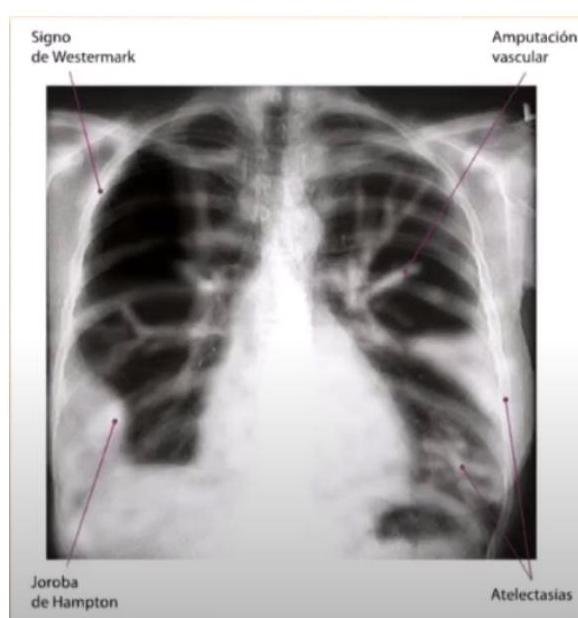

# ENFERMEDAD TROMBOEMBÓLICA ## DEFINICIÓN El término trombosis se refiere a la formación de una masa anormal dentro del sistema vascular a partir de los componentes sanguíneos. La **Enfermedad Tromboembólica Venosa (ETV)** comprende un espectro de enfermedades que engloban la **Trombosis Venosa Profunda (TVP)** y la **Tromboembolia Pulmonar (TEP)**; ambas comparten los mismos factores predisponentes. La TVP es una oclusión de los vasos pulmonares debido a un coágulo sanguíneo; el **95%** de los casos ocurre en el sistema venoso profundo de los miembros inferiores y posteriormente el émbolo se deposita en el área pulmonar. Cuando una TVP proximal no es tratada, ocurre una TP en el **33%** de los casos y otro **33%** presenta un embolismo subclínico. Otros orígenes de émbolos son las venas pélvicas, las extremidades superiores y las cavidades cardíacas derechas.  # FISIOPATOLOGÍA El proceso de trombosis involucra diversos factores que predisponen a un individuo a sufrir una oclusión trombótica, los cuales fueron descritos por Virchow desde el siglo XIX. ## TRÍADA DE VIRCHOW: - Lesión endotelial (Trauma, cirugía, fractura reciente, evento previo de TVP) - Éstasis o alteración del flujo sanguíneo (inmovilidad, obesidad, ICC, aumento PVC) - Estado hipercoagulable de la sangre (embarazo, postparto, ACO, cáncer, quemaduras severas) ## Triada de Virchow  Durante el episodio agudo se pueden apreciar las siguientes alteraciones fisiopatológicas: 1. Alteración del intercambio gaseoso: **AUMENTO DEL ESPACIO MUERTO FISIOLÓGICO** (zona que está siendo ventilada, pero no perfundida) por desequilibrio V/Q en el pulmón no obstruido (más perfusión que ventilación) y por shunt derecha a izquierda, que puede ocurrir a nivel intrapulmonar o intracardíaco. 2. Hiperventilación alveolar por estímulo reflejo nervioso. 3. Aumento de la resistencia al flujo aéreo por broncoconstricción de las vías aéreas distales al bronquio obstruido. 4. Disminución de la distensibilidad pulmonar por edema, hemorragia o pérdida de surfactante. 5. Aumento de la resistencia vascular pulmonar por obstrucción vascular o liberación de agentes neurohumorales como la serotonina por las plaquetas. 6. Disfunción ventricular derecha. El fracaso ventricular derecho es la causa de muerte más habitual de la TEP. A medida que aumenta la resistencia vascular pulmonar, aumenta la tensión del VD, mayor dilatación y disfunción ventricular. # EPIDEMIOLOGÍA - La ETV está ubicada en el 3er lugar como causa de muerte cardiovascular (después de enfermedad coronaria e isquemia cerebral). - Es un trastorno multifactorial, con incidencia anual de 1-2 por cada 1,000 personas. - Más frecuente en hombres. - Asociada a la edad con incremento a 1 por cada 100 personas en mayores de 55 años. - Un 20 % de quienes padecen ETV no tienen factores de riesgo asociados. FACTORES DE RIESGO | RIESGO | ANTECEDENTE | | :-------- | :--------------------------------------------------------------------------------- | | **ALTO** | Fractura de cadera o miembros inferiores <br> Cirugía **ORTOPÉDICA** <br> Prótesis de cadera <br> Cirugía mayor <br> Politrauma <br> IAM <br> Lesión de médula espinal | | **MODERADO** | Artroscopia <br> Catéter central <br> Quimioterapia <br> Insuficiencia cardíaca congestiva <br> Tratamiento hormonal <br> Embarazo <br> Trombofilia | | **BAJO** | Reposo en cama <br> Inmovilidad <br> Edad avanzada <br> Laparoscpia <br> Obesidad <br> Venas varicosas <br> Viajes en avión de largo recorrido <br> Síndrome antifosfolípido <br> Hiperhomocisteinemia <br> Policitemia primaria <br> EPOC | La resistencia a la proteína C activada (Factor V de Leiden) es el estado de hipercoagulabilidad hereditario más frecuente en el TEP, seguido de las mutaciones del gen de la protrombina. Pero estos factores genéticos solo justifican 1/5 casos de TEP y la mayoría de los que tienen estos factores genéticos nunca desarrollan ETV. # CLÍNICA ## TVP **DOLOR EN LA PANTORRILLA**: de inicio insidioso, que tiende a empeorar con el tiempo y se acompaña de palpación dolorosa. - La TVP masiva es fácil de reconocer. El paciente presenta **EDEMA DE MUSLO** con palpación dolorosa en zona inguinal y sobre la vena femoral común. - La TVP de miembros superiores puede producir empastamiento de la fosa supraclavicular, aumento de diámetro del miembro o circulación colateral en la región anterior del tórax. ## TEP **DISNEA**: generalmente súbita, es el síntoma más frecuente. Puede aparecer síncope o hipotensión brusca de causas no aclaradas. **DOLOR PLEURÍTICO**: aparece posterior a la disnea, siendo el segundo síntoma más frecuente. Taquicardia y Taquipnea: son signos constantes. Otros: hemoptisis, opresión torácica, broncoespasmo. | | | | :--------------- | :------------------------------------------------------------------------ | | **TEP Masivo** | Se presenta con hipotensión o choque. Suele ser TEP de gran tamaño o difusos. | | **TEP Moderado / Grande** | Sin hipotensión ni choque <br> Signos ecocardiográficos de sobrecarga de VD o elevación de marcadores de daño miocárdico | | **TEP Moderado / Pequeño** | Tensión arterial y función ventricular derecha normales. | # DIAGNÓSTICO ## PROBABILIDAD CLÍNICA La estimación de la probabilidad clínica es el primer eslabón en la aproximación diagnóstica del TEP. El diagnóstico es difícil debido a lo inespecífico de la clínica. Lo primero que se debe hacer es determinar la probabilidad clínica, pues una probabilidad clínica baja de TVP o moderada/baja de TEP permiten descartar la enfermedad si el Dímero D es negativo sin utilizar otras pruebas de imagen. Dada la gravedad del proceso, un alto grado de sospecha clínica basta para iniciar anticoagulante. ## SISTEMA DE WELLS DE PROBABILIDAD CLÍNICA | Síntomas o signos de Trombosis Profunda | 3 | | :------------------------------------------------------------ | :-- | | Diagnóstico alternativo menos probable | 3 | | FC >100 lpm | 1.5 | | Cirugía o inmovilización en las 4 semanas previas | 1.5 | | Episodio de tromboembolismo pulmonar o trombosis profunda previa | 1.5 | | Hemoptisis | 1 | | Cáncer | 1 | | PROBABILIDAD BAJA | 0-1 punto | | :---------------------- | :----------- | | PROBABILIDAD INTERMEDIA | 2-6 puntos | | PROBABILIDAD ALTA | >7 puntos | ## RADIOGRAFÍA Una placa normal o con escasas alteraciones aumenta la sospecha de TEP, aunque lo habitual es que existan anomalías: - Elevación del hemidiafragma. - Atelectasias. - Anomalías parenquimatosas pulmonares. - Derrame pleural escaso y serohemático. **SIGNO DE WESTERMARK**: Oligohemia focal que produce hipertensión pulmonar. **JOROBA DE HAMPTON**: condensación parenquimatosa triangular de base pleural. Asociado a TEP con infarto y presenta derrame pleural de pequeña cuantía.  # ELECTROCARDIOGRAMA Las alteraciones más comunes son Taquicardia Sinusal y Anomalías Inespecíficas en el ST-T de V1 - V4. Puede haber signos de sobrecarga derecha como patrón SI,QIII,TIII (S en la derivación I, Q y T invertida en la III). ## LABORATORIO Marcadores Cardíacos: La elevación de Troponinas aumenta el riesgo de complicaciones y mortalidad en TEP estables. Gasometría: existe hipoxemia y aumento de gradiente alveoloarterial. - Puede haber pacientes sin antecedentes de patología pulmonar con PO2 y D(a-a)O2 normales. - La PaCO2 suele estar baja (hipoventilación refleja) - **ALCALOSIS RESPIRATORIA**. ## DÍMERO D Sensibilidad del **95%** (85%-99%) y especificidad del **50%** (29-71%) y un valor predictivo negativo del 95 al 100 %. Son generados por la acción del Factor VIII de coagulación sobre los monómeros y multímeros de fibrina. Su elevación revela la presencia de fibrinólisis endógena, pero no es específico de TEP. Aumenta también en: IAM, neumonía, fallo derecho, carcinomas, cirugía, inmovilizaciones. Se debe determinar mediante **ELISA**. Tiene un elevado valor predictivo negativo, especialmente si se combina con la probabilidad clínica del Sistema Wells - Probabilidad Baja/Intermedia y Dímero D <500 \rightarrow se descarta TEP. No es muy útil en pacientes con cáncer o cirugía reciente ya que la mayoría tiene >500 ng / ml. ## TAC ESPIRAL CON CONTRASTE ## 1ª elección: ante la sospecha de TEP - Tiene sensibilidad mayor del **80 %** y una especificidad mayor del **90 %**. - Visualiza arterias del sexto orden. - Tiene contraindicación en la IR o alergia al contraste. Si el resultado es normal y la sospecha clínica es alta - **ANGIOGRAFÍA PULMONAR**. ## ANGIOGRAFÍA PULMONAR - Era el **GOLD STANDARD** hasta antes de la APTC. - Puede precisarse para el diagnóstico cuando hay una alta sospecha clínica y los otros estudios (TC Espiral, Ecografía) son negativos. - Se debe realizar en pacientes que se vayan a someter a algún tipo de intervención como una embolectomía o una trombolisis dirigida por catéter. # ANGIOGRAFÍA POR TOMOGRAFÍA La **APTC** es la prueba que actualmente se considera **GOLD ESTÁNDAR** al ser menos invasiva. ## GAMMAGRAFÍA DE PERFUSIÓN PULMONAR  - Prueba de segunda línea, indicada en casos en los que no se pueda realizar la Tomografía. - Un resultado normal excluye el diagnóstico de TEP. - Un resultado anormal, se debe combinar con el de la gammagrafía de ventilación y así determinar la probabilidad gammagráfica de TEP. - Una gammagrafía de alta probabilidad diagnóstica es la que presenta 2 o más defectos de perfusión segmentarios con gammagrafía de ventilación y radiografía de tórax normales. ## ECOCARDIOGRAFÍA - Baja sensibilidad para detectar TEP, puede ser útil en casos de sospecha de TEP clínicamente graves, puesto que valora la función ventricular derecha y visualiza trombos importantes. - Se realiza transesofágica o transtorácica. ## ECOGRAFÍA VENOSA - Es la prueba no invasiva más utilizada en la actualidad para valorar TVP y ha llevado al desuso a la pletismografía y a la flebografía isotópica. - Es fiable en sintomáticos ambulatorios con sospecha de TVP; en sintomáticos y hospitalizados, pero la tasa de detección de TVP es mucho más baja. | | | | :------------------- | :------------------------------------------------------------------------------------------ | | **TROMBO NO MASIVO** | Presenta un excelente pronóstico y es la más frecuente. | | **TROMBO SUB-MASIVO** | Presenta disfunción del ventrículo derecho del corazón, pero con una presión arterial normal. | | **TROMBO MASIVO** | Afectación de al menos la mitad de los vasos del pulmón. | # TRATAMIENTO El tratamiento primario consiste en la disolución del coágulo, ya sea mediante trombolisis o mediante embolectomía. La anticoagulación o el filtro de vena cava constituyen más bien una prevención secundaria a un nuevo episodio. - El tratamiento anticoagulante es el factor más importante en la terapéutica de ETV. ## HEPARINAS ## HEPARINA NO FRACCIONADA (HNF) - Acelera la acción de la antitrombina III e inactiva el factor Xa, por lo que se **previene la formación de un trombo adicional** y permite que la fibrinolisis endógena disuelva algo del émbolo. - Requiere monitorizar **TTPa**, que debe duplicarse. - Su acción puede ser revertida con **SULFATO DE PROTAMINA**. - Se utiliza fundamentalmente en TEP con compromiso hemodinámico junto a los fibrinolíticos. ## HEPARINA DE BAJO PESO MOLECULAR (HBPM) - Se administra por vía subcutánea. - Tiene una vida media plasmática más larga, ya que interactúa menos con las plaquetas y las proteínas. - Apenas se unen a la antitrombina III y ejerce su efecto fundamentalmente inactivando el factor Xa. - La monitorización del TTPa y el ajuste de dosis no suele ser necesaria, salvo en casos de obesidad, embarazo o IR grave. - En situaciones hemodinámicamente estables es tan eficaz y segura como la HNF. ## FONDAPARINUX Es un inhibidor selectivo del factor Xa que se administra por vía subcutánea una sola vez al día. No necesita controles de coagulación, pero debe reducirse su dosis en IR. # ANTICOAGULANTES ORALES Inhiben la activación de los factores de coagulación dependientes vitamina K (II, VII, IX y X). ## Fármaco más utilizado - WARFARINA - Se administra desde el día siguiente del inicio de la heparina y se mantiene simultáneamente durante al menos 5 días. - El mantenimiento requiere de un **INR entre 2-3**. - Si el paciente está hemodinámicamente estable y con adecuada función del Ventrículo derecho, los anticoagulantes son suficientes para buenos resultados. **CONTRAINDICADOS EN EL EMBARAZO** por teratogenia de los cumarínicos. El acenocumarol junto con la HNF se inicia hasta después del parto, independientemente de la heparina utilizada. ## TROMBOLÍTICOS 1ª elección en **TEP MASIVO** (única indicación aprobada) y en la TVP Iliofemoral masiva o de cava inferior. - Debe realizarse de forma precoz, aunque puede haber respuesta hasta 2 semanas tras el TEP. - Objetivo: rápida lisis del trombo, acortando la fase de alto riesgo y reduciendo la mortalidad. - Fármacos empleados: Urocinasa, Estreptocinasa, Activador Tisular del Plasminógeno (rTPA). ## TRATAMIENTO INVASIVO Colocación de filtros en la cava inferior, embolectomía (si hay compromiso hemodinámico grave que no responde a fibrinolíticos) o la tromboendarterectomía (en los casos de hipertensión pulmonar crónica secundaria a TEP con clínica grave). ## Indicaciones del filtro en cava inferior: - Contraindicaciones o complicaciones de anticoagulación en pacientes con ETV o alto riesgo de la misma. - TEP recurrente a pesar de anticoagulación. - Gran trombo flotante en vena cava inferior. - Realización simultánea de embolectomía o tromboendarteriectomía. - Profilaxis en riesgo extremo. Los filtros evitan TEP en la fase aguda, pero a largo plazo aumentan el riesgo de TVP, por lo que los pacientes que lo usen, deben permanecer anticoagulados. ## DURACIÓN DE ANTICOAGULANTES Se recomienda **3 - 6 meses** cuando es el primer episodio en pacientes con factores de riesgo reversibles. En caso contrario, mantenerlo indefinidamente, valorando periódicamente si el riesgo de sangrado supera al beneficio de la anticoagulación.  # DIAGNÓSTICO TEP  (c) Copyright 2021-2022 Joyas ENARM - Todos los derechos reservados -